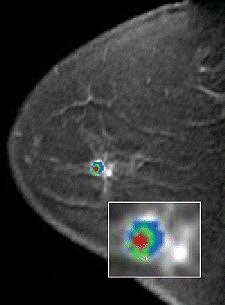

| A 49-year-old woman with mammographically occult contralateral breast cancer detected on MRI. Above, initial contrast-enhanced sagittal MR image. Below, CAD overlay shows lesion as having significant enhancement and mixed pattern of washout, plateau, and persistent delayed enhancement. If pixel value on delayed series decreases by more than 10% of its immediate contrast-enhanced value, that pixel is color-coded red on monitor, indicating washout of contrast material. If pixel value increases by more than 10%, it is color-coded blue on monitor, indicating persistent enhancement. If pixel value does not change in either direction by more than 10%, it is color-coded green for plateau enhancement. |

One radiologist recorded whether the study lesion was marked as having significant enhancement by CAD at 50%, 80%, and 100% enhancement threshold levels. For each lesion significant enhancement, the percent values of washout, plateau, and persistent enhancement were also recorded.

According to the results, 24 lesions were identified by pathology as benign and nine were malignant. "All malignant lesions showed significant enhancement using the program at all thresholds, producing a sensitivity of 100%," the authors wrote.

"False-positive rates for the computer-aided assessment compared with the original radiologist assessment were reduced by 25% at a 50% threshold, 33% at an 80% threshold, and 50% at a 100% threshold for enhancement," they added.